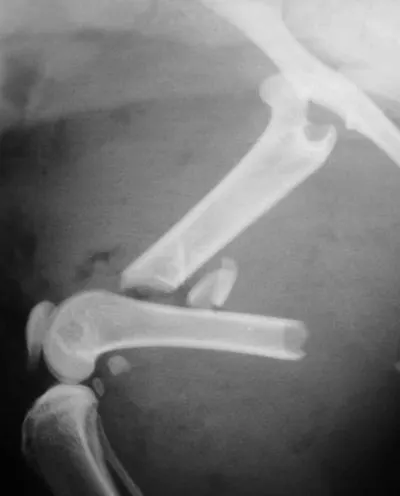

The combination of an IM pin and a bone plate has been found to be an ideal implant system for biologic management of comminuted fractures (Figure 1A) in dogs7 and cats. Adding an IM pin to the plate (Figures 1B, C) significantly increases stiffness and the estimated number of cycles to fatigue failure when compared with a plate-only system.

Adding an IM pin to a bone plate has been shown to reduce strain on the plate two-fold and subsequently increase the fatigue life of the plate-rod system 10-fold compared with the plate alone.2 In the canine femur, plate strain is reduced by approximately 19%, 44%, and 61% with the addition of an IM pin occupying 30%, 40%, and 50% of the marrow cavity, respectively.3

The IM pin is applied first. It can be used to assist distraction of the fracture as it engages the distal fragment. The pin provides axial alignment and provides partial stability for application of the plate.

The surgeon must be careful to attain rotational alignment before placing the screws of the bone plate. Only two to three screws are needed in the proximal and distal fragment. Monocortical screws are placed if the screw cannot be directed to avoid the IM pin. Open screw holes are protected by the IM pin and early bone callus, decreasing the chance of plate breakage.